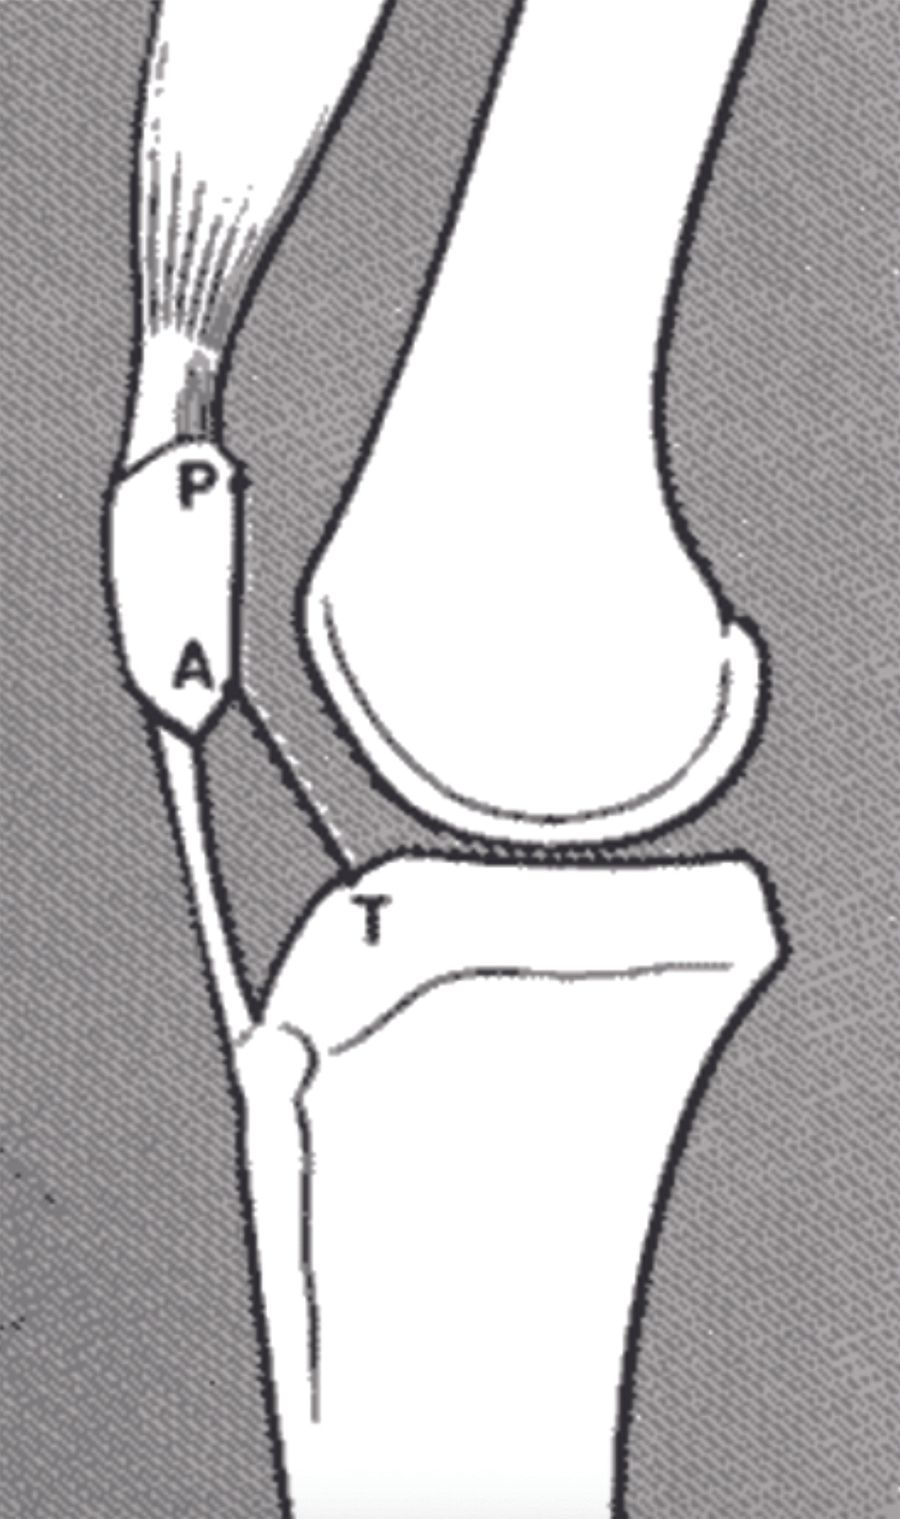

Technique Pourquoi et comment nous resurfaçons la rotule , Myles Coolican Sydney Orthopaedic Research Institute (SORI), Sydney, Australia / , Thomas Neri Service de chirurgie orthopédique, CHU Saint-Etienne, Saint-Etienne, France N°270 - Janvier 2018 ● 6 min de lecture